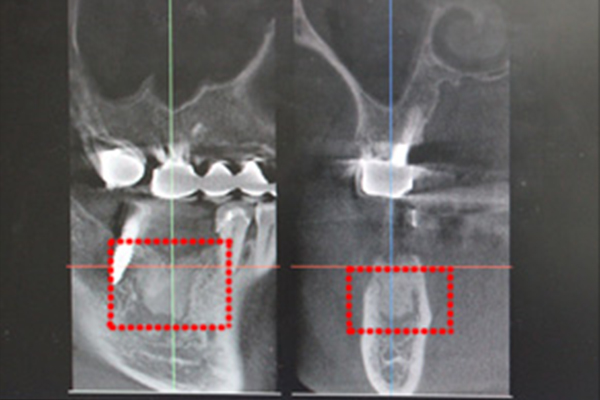

CGF治療4ヶ月後

硬い骨ができあがっています。